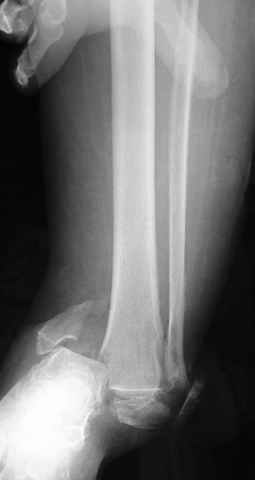

A propos fibular fixation if one is eager to stabilize it separately. In the fracture pattern a way of closed fixation by V-shaped stressed wire (advanced by colleagues from Moscow, prof. Lazarev A.F. et al.) must be excellent. We use indirect closed reduction by the external fixator. Example attached, that fibular fracture is even more suitable for plating but the wire did the job.

Второй случай сделан из одного разреза

Дж